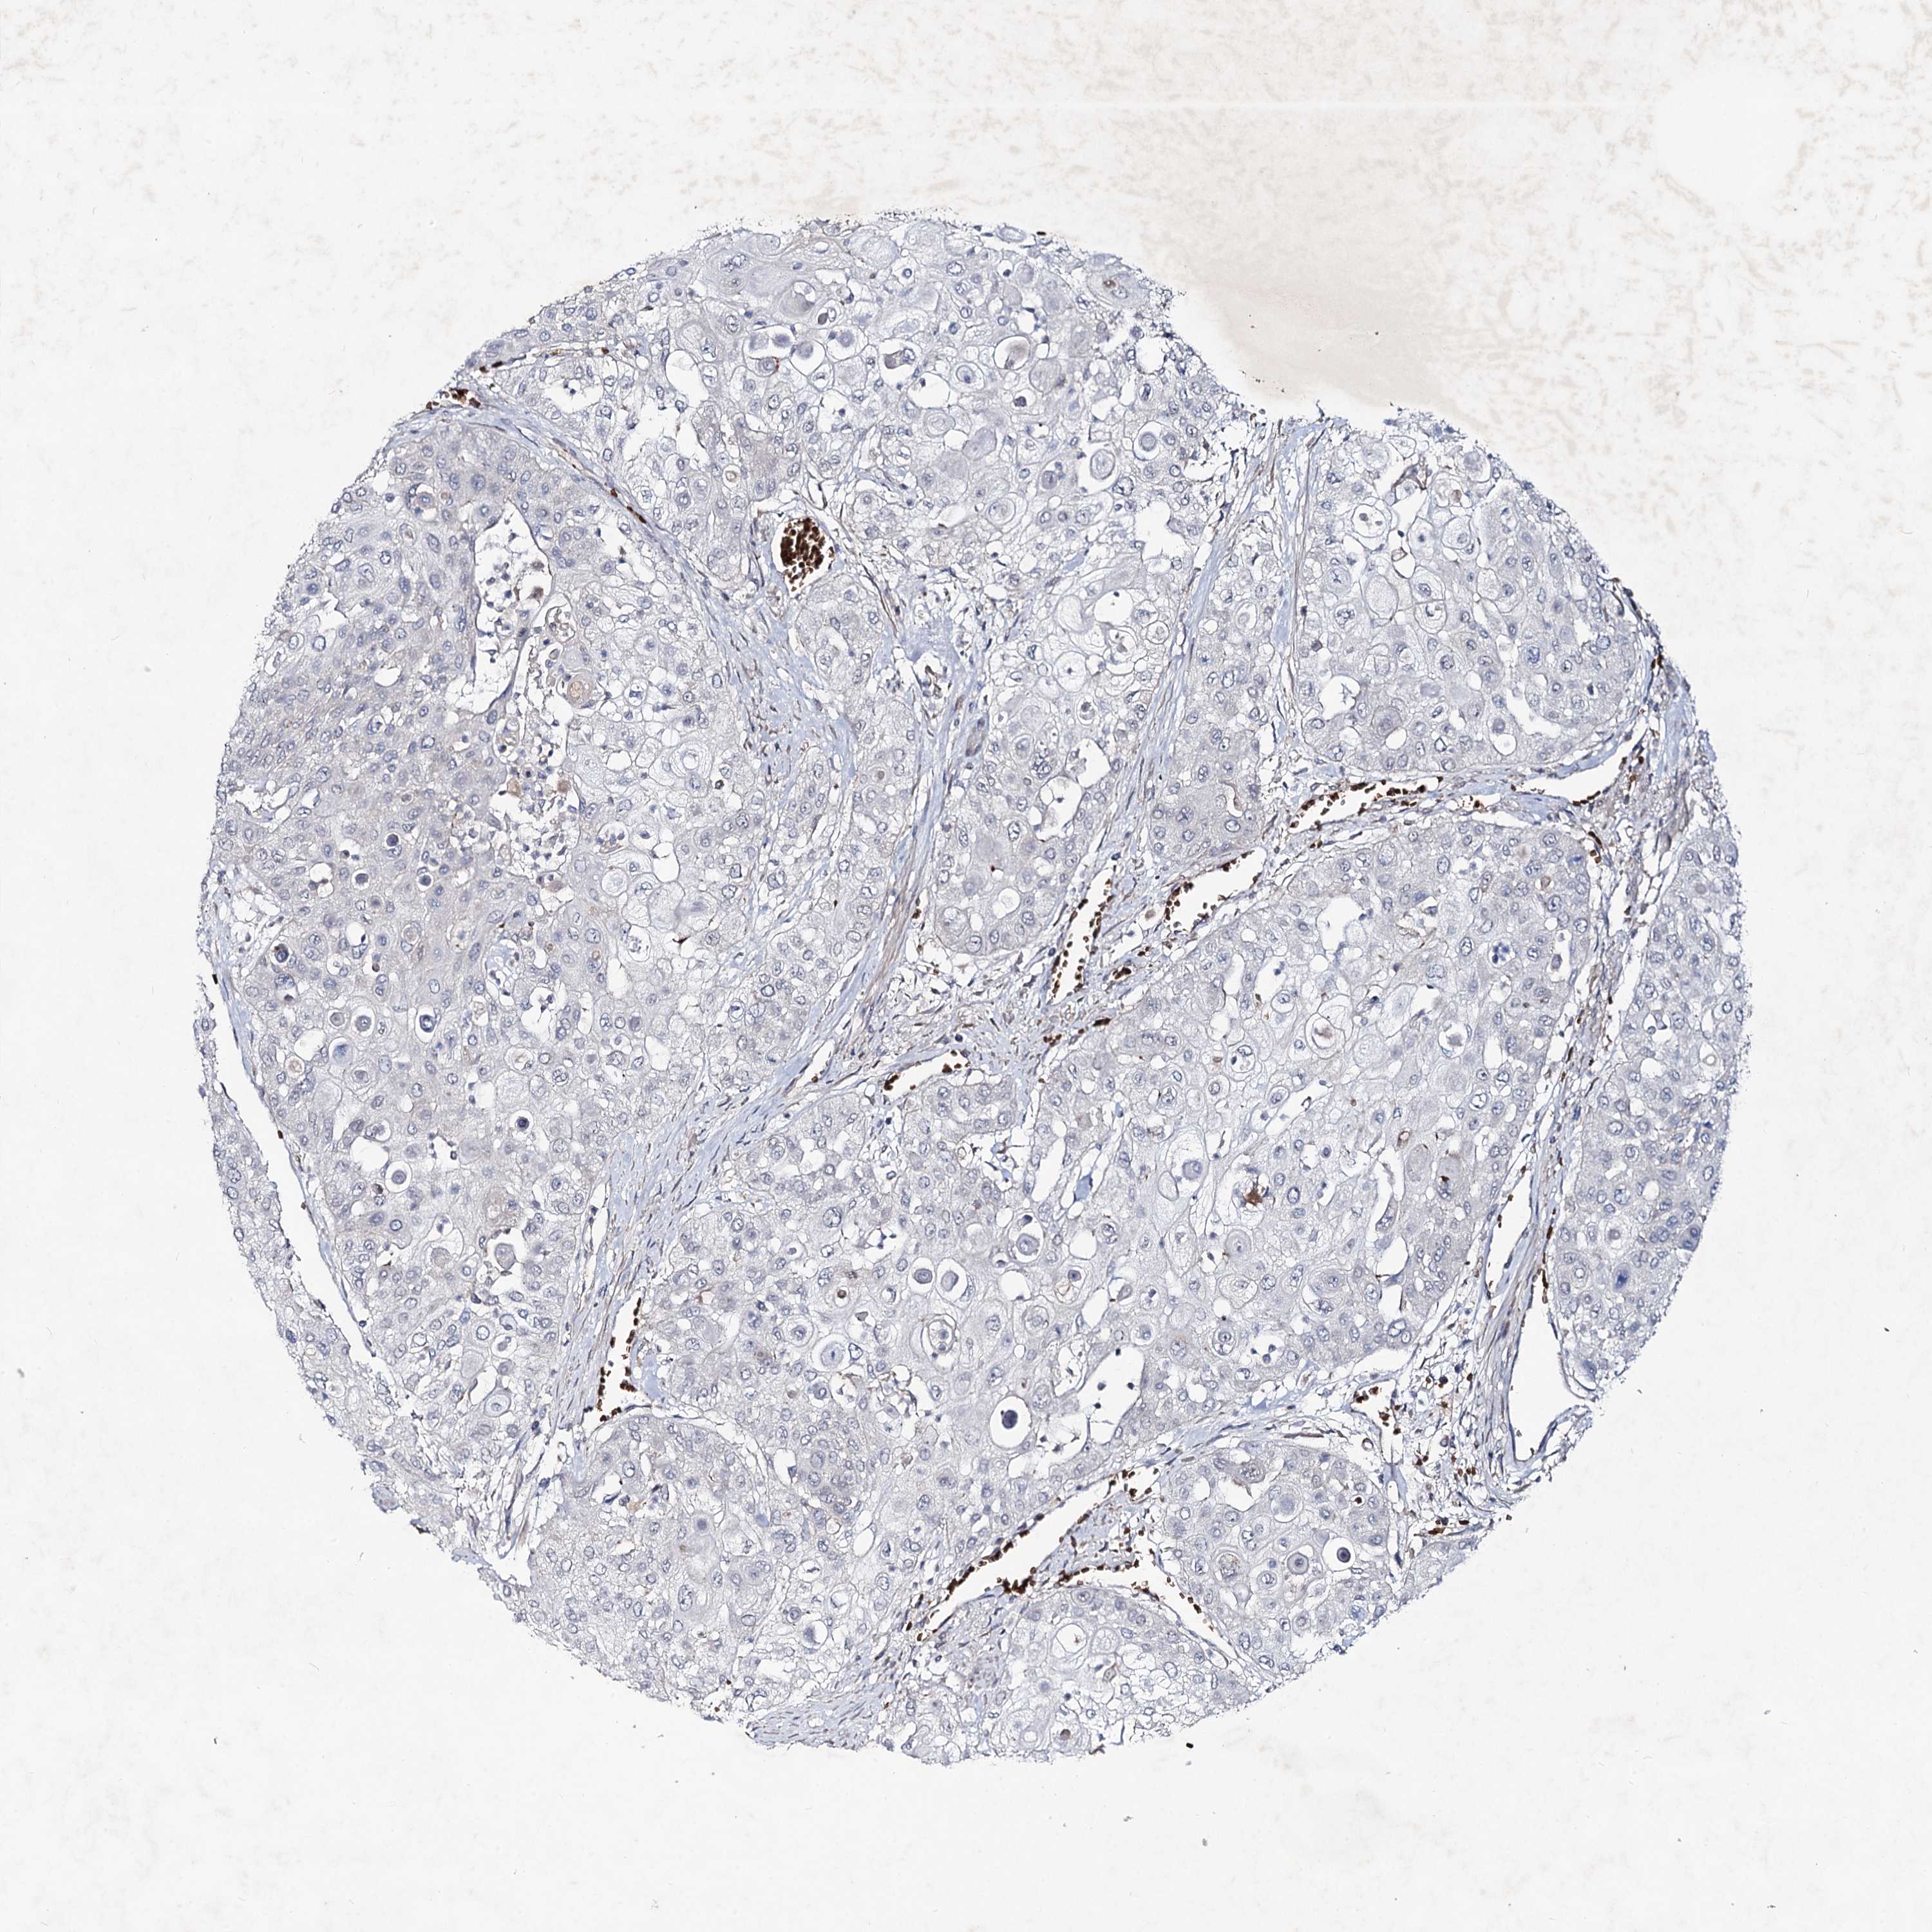

UROTHELIAL CANCER - Protein expressioni

A mouse-over function shows sample information and annotation data. Click on an image to view it in a full screen mode. Samples can be filtered based on level of antibody staining by selecting one or several of the following categories: high, medium, low and not detected. The assay and annotation is described here.

Note that samples used for immunohistochemistry by the Human Protein Atlas do not correspond to samples in the TCGA dataset.

Antibody stainingi

Antibody staining in the annotated cell types in the current human tissue is reported as not detected, low, medium, or high, based on conventional immunohistochemistry profiling in selected tissues. This score is based on the combination of the staining intensity and fraction of stained cells.

Each image is clickable and will lead to virtual microscopy that enables deeper exploration of all samples and also displays staining intensity scores, fraction scores and subcellular localization as well as patient and tissue information for each sample.

Antibody HPA039343

Antibody HPA040048

Urothelial carcinoma, High grade

Urothelial carcinoma, Low grade